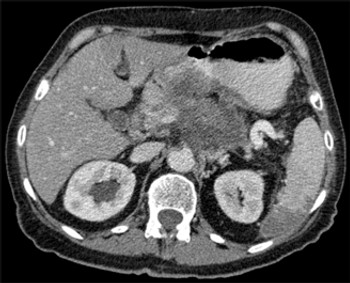

Developing a scoring system for staging patients with hepatic colorectal metastases is important for prognosis and for identifying those who will benefit from additional systemic therapy.

Due to advances in chemotherapy, biologic therapy, and the development of liver-oriented treatment options, the survival of patients with metastatic cancer has more than doubled, and increasing numbers of patients have been cured, even among those with advanced disease.

This article will review the current practice of hepatic resection for colorectal liver metastases, including the possibility of combined resection of hepatic metastases at the time of resection of the primary cancer.